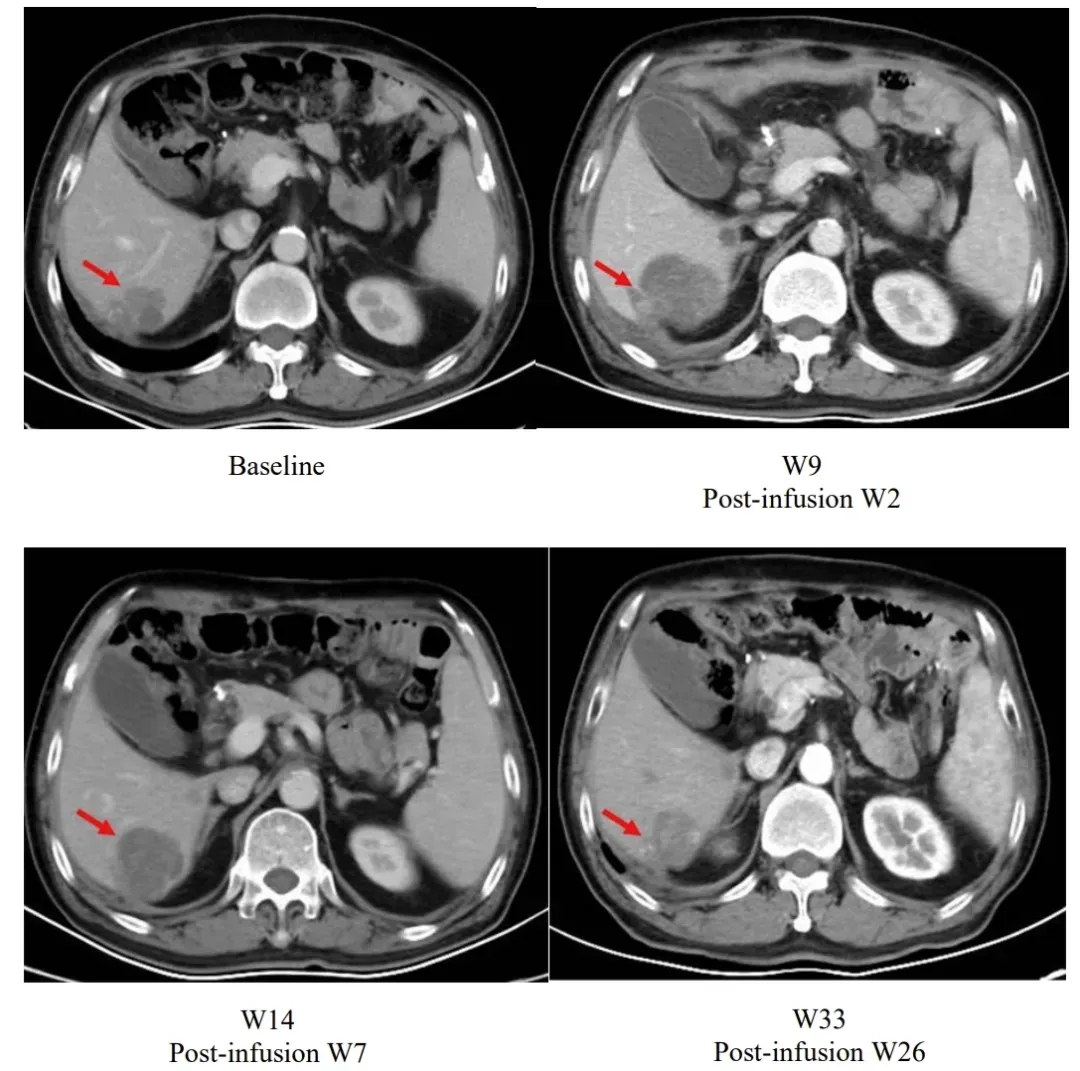

值得一提的是,研究中一项典型案例展现了独特的治疗响应过程:患者在输注satri-cel后第2周,肝脏病灶较基线有所增大;但在后续持续随访中,病灶逐步缩小,至输注后第26周时,已显著小于基线水平(详见下图)。

▲图源“The Lancet”,版权归原作者所有,如无意中侵犯了知识产权,请联系我们删除